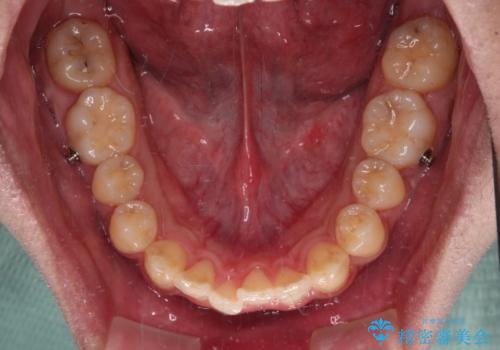

前歯のクロスバイト インビザラインによる矯正治療

- 上下のクロスバイトと前歯のデコボコを気にして来院された患者様です。

インビザラインを用い、IPR(歯と歯の間を削る)と歯列全体を拡大させることで、歯並びを整えていくこととしました。